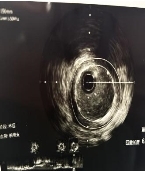

依托这一精准的可视化导航,主刀医生像拿着高清地图开车一样,确定病变范围、测量血管参数,制定个体化手术方案。最终,支架被精准植入,完美覆盖病变部位,成功开通了闭塞、狭窄的心脏血管,恢复心脏正常供血。手术全程顺利,术中术后无任何并发症。术后复查显示:患者心脏血流通畅,心肌供血恢复正常,原本的不适症状彻底消失。

(术后)